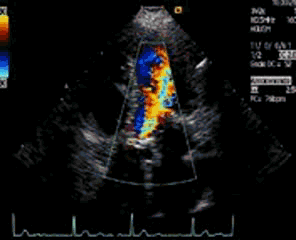

Así que lo primero será poner la caja de color para valorar aceleraciones extrañas e insuficiencias.

En el clip 12 puedes ver una insuficiencia de esta válvula. Para cuantificarla, además de la impresión que tengamos por la cantidad del chorro de color retrógrado, podemos ir “interrogando” al ventrículo izquierdo en situaciones cada vez más apicales para ver mediante el espectro pulsado hasta dónde llega la regurgitación. También es posible valorar la pendiente de esa regurgitación en el Doppler continuo. Y por último, si la insuficiencia es severa, tendremos que valorar también con Doppler espectral en los planos supraesternales.

Clip 12.

The interest of this plane is to assess the aortic valve and fundamentally its functionality through color Doppler and the measurements that we will obtain by means of pulsed and continuous spectral Doppler. So the first thing is to put the color box to assess strange accelerations and inadequacies. In clip 12 you can see an insufficiency of this valve. To quantify it, in addition to the impression we have for the amount of retrograde color jet, we can «interrogate» the left ventricle in increasingly apical situations to see through the pulse spectrum how far the regurgitation arrives. It is also possible to assess the slope of this regurgitation in continuous Doppler. And finally, if the insufficiency is severe, we will also have to evaluate with spectral Doppler in the suprasternal planes.